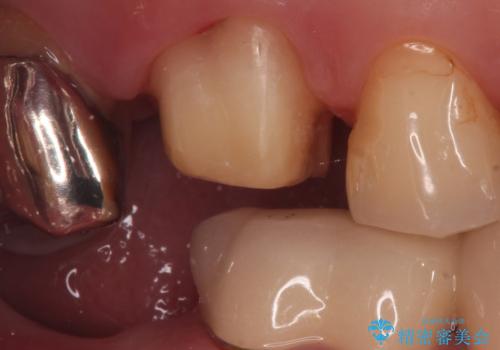

割れた被せ物を作りなおしたい

- 他院で装着した被せ物が割れたとのことで来院されました。

被せ物の厚みが確保されていなかったため、向かいの歯とのスペースを確保するように修正していきます。

被せ物の厚みが十分に確保できていないと、材料によっては今回のように割れてしまうことがあります。

被せ物の材料を変えるか、厚みを確保することでそのリスクを抑えることができます。

今回はセラミックでの再治療をご希望されたため被せ物の厚みを確保することで対応しました。